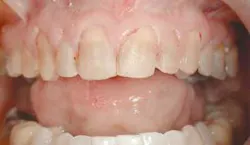

The final result of this case sees an improvement in all of the original objectives (Figs. 12, 13, 14). Our patient wanted a lighter, wider smile that would cover the darkness she had lived with her entire life. Needless to say, she was ecstatic with the end results (Figs. 15, 16).